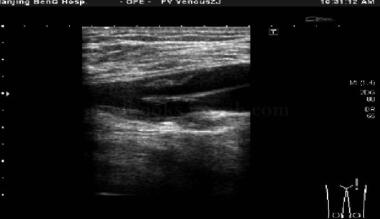

血、便常规正常。尿常规:尿蛋白+++,尿糖++。生化:血K+3﹒33mmol/L,TG12.37mmol/L,LDL 0﹒82mmol/L,ALT93.9U/L,GGT173U/L,CK310U/L。凝血功能:APTT23.5秒,PT10秒。糖化血红蛋白8.2%。心电图提示心房颤动,Ⅰ、Ⅱ、aVL、V4~V6导联T波倒置。胸片提示双肺纹理增多。颈动脉彩超:双侧颈动脉硬化伴斑块形成(硬斑),左侧颈动脉内中膜增厚约1.8mm。心脏彩超:LAD 44mm,LVDd57mm,IVS14mm,LVPW13mm,EF61%,左心房、左心室增大,高血压性心脏病改变,左心室舒张功能减退。双下肢动脉造影示左股深动脉近端闭塞,右股深动脉多处狭窄,最重处达80%。下肢血管彩超见图1。肢体动脉硬化检查见图2。

图1 下肢血管彩超:双侧下肢动脉血管内膜病变并管腔狭窄伴多发斑块